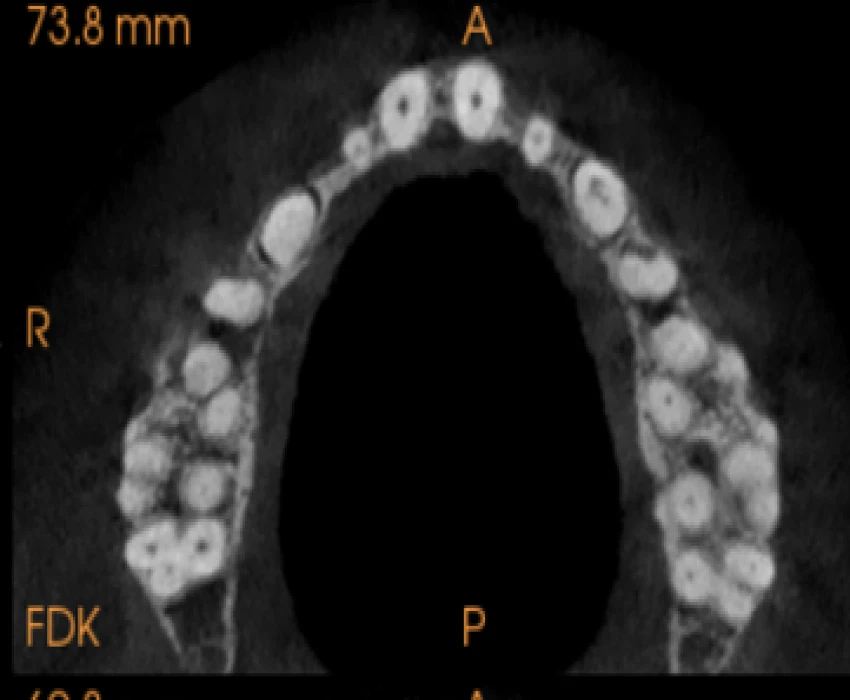

On intra-oral examination generalized loss of cervico-occlusion height and colour of the teeth appeared opalescent and brown in colour.

On the basis of history, clinical examination, and radiographic investigation final diagnosis was given as Amelogenesis imperfecta- Hypoplastic Type.

In patients with hypoplastic amelogenesis imperfecta, the basic alteration centers on inadequate deposition of enamel matrix. In the generalized pattern, pinpoint-to-pinhead–sized pits are scattered across the surface of the teeth and do not correlate with a pattern of environmental damage. The buccal surfaces of the teeth are affected more severely. Both dentitions, or only the primary teeth, may be affected. All of the teeth may be altered, or only scattered teeth may be affected.